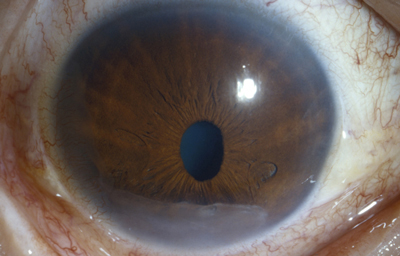

Colobomas típicos con diferentes grados de defecto en el desarrollo

Colobomas Atípicos.

Archivo Fotográfico Dr. Francisco Barraquer

Archivo Fotográfico Dr. Francisco Barraquer